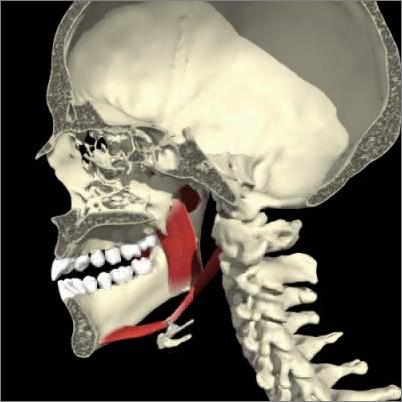

Patologie A.T.M.

L'articolazione temporo mandibolare (ATM) è un'articolazione molto complessa e la sua patologia, causata da disfunzioni muscolari cinetiche (del movimento masticatorio) puo' interessare sia la componente ligamentosa/meniscale (lussazione, sublussazione , incoordinazione meniscale , lassità ligamentosa) , che la componente ossea(artriti , artrosi ). L'ATM è al centro di un complesso sistema che coinvolge ossa-muscolo e denti e quindi una sua patologia pu' determinare ripercussioni molto importanti ed invalidanti di piu' apparati . Per i motivi sopra citati è molto importante diagnosticare precocemente e con estrema accuratezza specialistica (esame gnatologico) i disturbi e le disfunzioni neuro-muscolari dell'atm che molto spesso necessitano di un approccio multidisciplinare (reumatologo, neurologo, fisioterapista...). Nei nostri centri è disponibile la figura dello gnatologo atto alla diagnosi e alla eventuale terapia di queste patologie .

![]() | ![]() | ![]() |